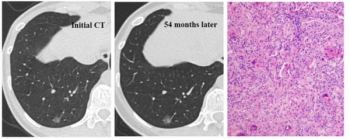

In a computed tomography (CT) study assessing over 450 patients who had lung adenocarcinoma resection, researchers noted zero recurrence at five years and 97.7 percent recurrence-free survival at seven years for patients with resected pure ground glass nodules.